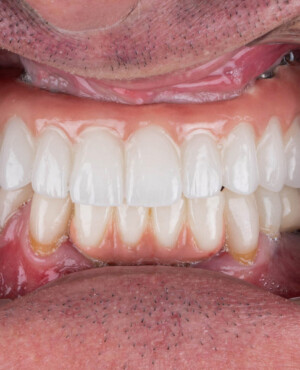

Protezarea pe implanturi dentare este soluția modernă, estetică și funcțională pentru înlocuirea dinților lipsă. Această procedură combină precizia chirurgicală cu tehnologia avansată de laborator pentru a reda pacienților zâmbetul natural, vorbirea clară și capacitatea de a mânca fără restricții.

La Clinica Dentară Dr. Grossu din Chișinău, oferim protezări pe implanturi dentare personalizate, realizate de o echipă multidisciplinară, cu ajutorul celor mai noi tehnologii digitale și materiale biocompatibile.

- Estetică superioară – imită perfect dinții naturali